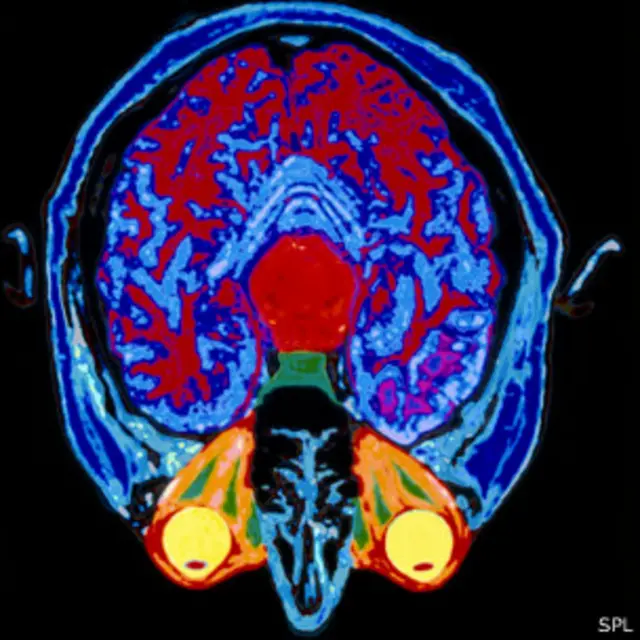

Usando una técnica llamada imagen por resonancia magnética funcional, los neurocientíficos pueden poner a alguien en un escáner y ver qué partes del cerebro se activan cuando hacen o piensan en algo.

Una simple acción, como cerrar y abrir el puño de la mano o decir unas pocas palabras requiere de la actividad de mucho más de una décima parte del cerebro. Incluso cuando se supone que no se está haciendo nada, el cerebro está haciendo mucho, ya sea controlando funciones como respirar y el palpitar del corazón, o recordando cosas por hacer. (1)